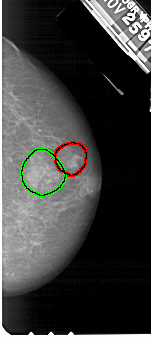

A_1529_1.RIGHT_MLO

RIGHT_CC LINES 5116 PIXELS_PER_LINE 2251 BITS_PER_PIXEL 12 RESOLUTION 43.5 OVERLAY

RIGHT_MLO LINES 5491 PIXELS_PER_LINE 2296 BITS_PER_PIXEL 12 RESOLUTION 43.5 OVERLAY

FILE: A_1529_1.RIGHT_MLO.OVERLAY

TOTAL_ABNORMALITIES 2

ABNORMALITY 1

LESION_TYPE MASS SHAPE OVAL MARGINS ILL_DEFINED

ASSESSMENT 4

SUBTLETY 4

PATHOLOGY MALIGNANT

ABNORMALITY 2